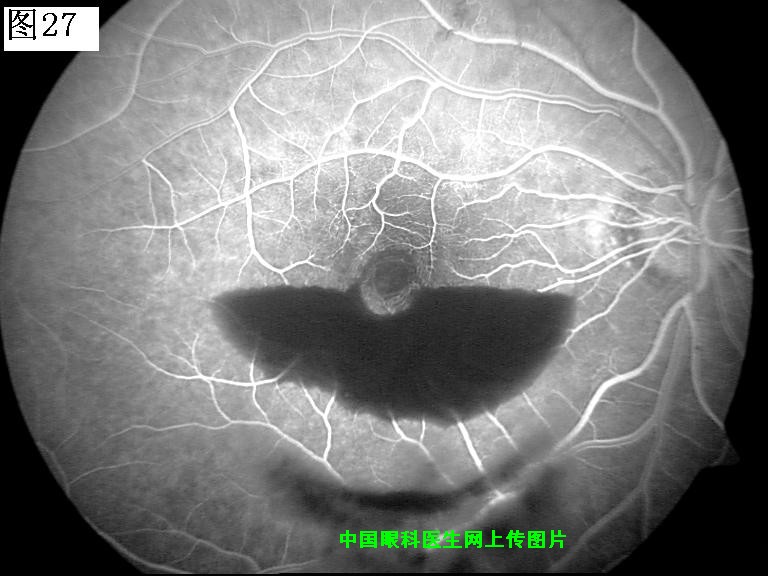

25 26 27 28